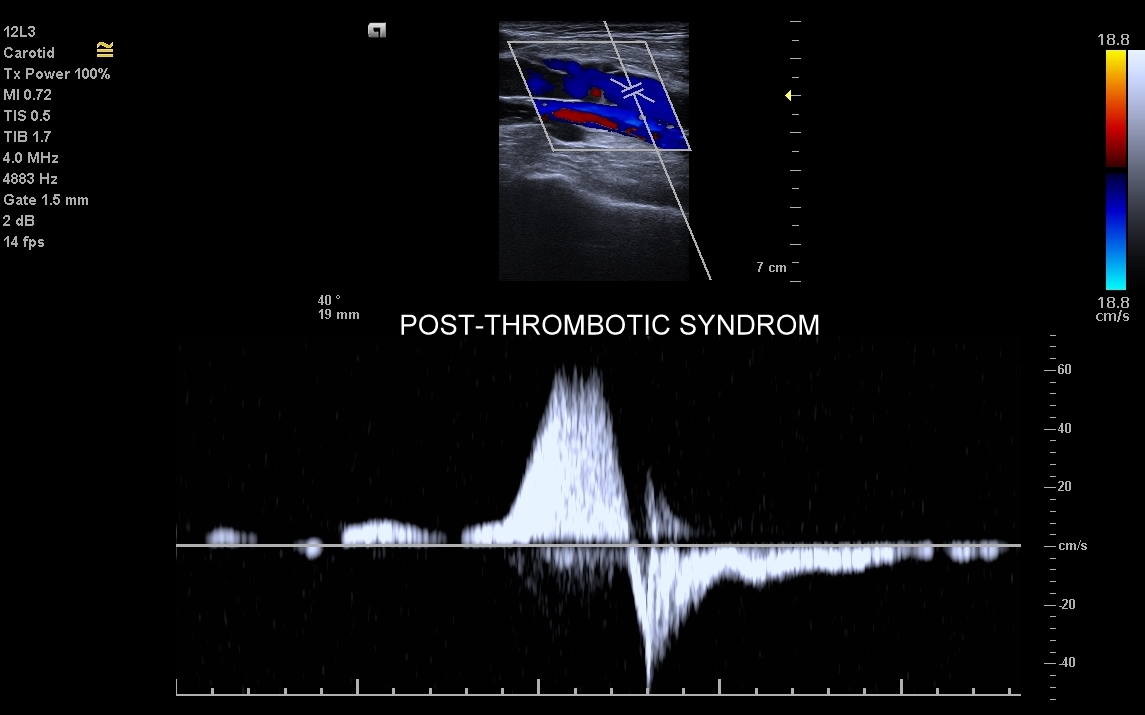

• zespół pozakrzepowy;

Badanie USG żył kończyn dolnych najczęściej wykonywane jest w ramach diagnostyki niewydolności żył powierzchownych oraz ich objawów w postaci pajączków żylnych, żylaków kończyn dolnych, obrzęków i owrzodzeń żylnych. Kolejnym pod względem częstości wskazaniem do badania Doppler żył jest podejrzenie zakrzepicy żył głębokich kończyn dolnych, monitorowanie leczenia zakrzepicy oraz ocena jej powikłań odległych. Powikłaniem nieleczonej zakrzepicy żył głębokich może być zespół pozakrzepowy manifestujący się masywnymi obrzękami kończyny i zaburzeniami troficznymi. Badanie USG Doppler żył kończyn dolnych często uzupełniane jest oceną układu żył centralnych w miednicy i jamie brzusznej. W tych obszarach również pojawiać się mogą żylne zmiany zakrzepowe, niedrożności żył, a nawet zmiany nowotworowe.

Czym jest zakrzepica żył? Zakrzepica żylna polega na powstaniu skrzepu wewnątrz naczynia żylnego i wtórnym rozwoju stanu zapalnego w okolicy naczynia. Choroba dotyczyć może układu powierzchownego żył lub żylaków, a w tym wypadku nie jest zwykle stanem niebezpiecznym; a także układu głębokiego żył, co z kolei jest stanem potencjalnie zagrażającym życiu, gdyż może sprowokować zatorowość płucną. Zakrzepica żył głębokich (ang. deep venous thrombosis DVT) częściej występuje w obrębie żył kończyn dolnych, następnie w obrębie żył biodrowych, rzadziej w żyle podobojczykowej i żyłach głębokich kończyny górnej. Przyczyny zakrzepicy żylnej są różnorodne i obejmują m. in. długie podróże, długotrwałe unieruchomienie, operacje ortopedyczne, chirurgiczne i szczękowe, urazy tkanek miękkich oraz złamania kości, genetycznie uwarunkowane trombofilie, nowotwory złośliwe, odwodnienie, infekcje miejscowe i ogólnoustrojowe. W przypadku zakrzepicy żyły podobojczykowej klasyczną jej przyczyną jest ucisk; w swojej praktyce klinicznej dr Szczepański spotkał się z zakrzepicą podobojczykową wywołaną m. in. przez ciężki plecak, wyciskanie sztangi na siłowni, czy przez uprawianie wspinaczki skałkowej. W warunkach szpitalnych zakrzepica żyły podobojczykowej lub żyły szyjnej wewnętrznej może pojawić się w wyniku zakładania cewników dożylnych. Sprawne wykrycie zakrzepicy w badaniu USG, a następnie wdrożenie odpowiedniej terapii uchronić może pacjenta przed powikłaniami ostrymi (np. zator płucny), jak i opóźnionymi (np. zespół pozakrzepowy).